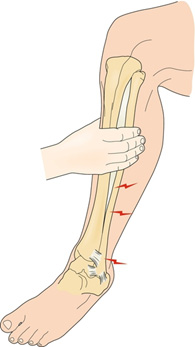

For all patients with ankle injuries, it is extremely important to rule out a Maisonneuve fracture.[9] Patients may recall a twisting motion to their ankle but not always. Patients may only report ankle pain with significant swelling, but it is important to examine the joints above and below the ankle. The “Squeeze Test” requires palpation of the tibia and fibula at the mid-calf level and if it returns positive for tenderness, it suggests a syndesmotic injury (Figure 2a). Additionally, one can perform an external rotation stress test which has the foot start in a neutral position followed by external rotation of the tibia. If there is tenderness with external rotation, syndesmotic injury is probable (Figure 2b). Proximal fibular tenderness suggests fracture. When both physical exam findings are present, Maisonneuve fracture is to be suspected.

Figure 2a: Squeeze Test

Figure 2b: External Rotation Stress Test